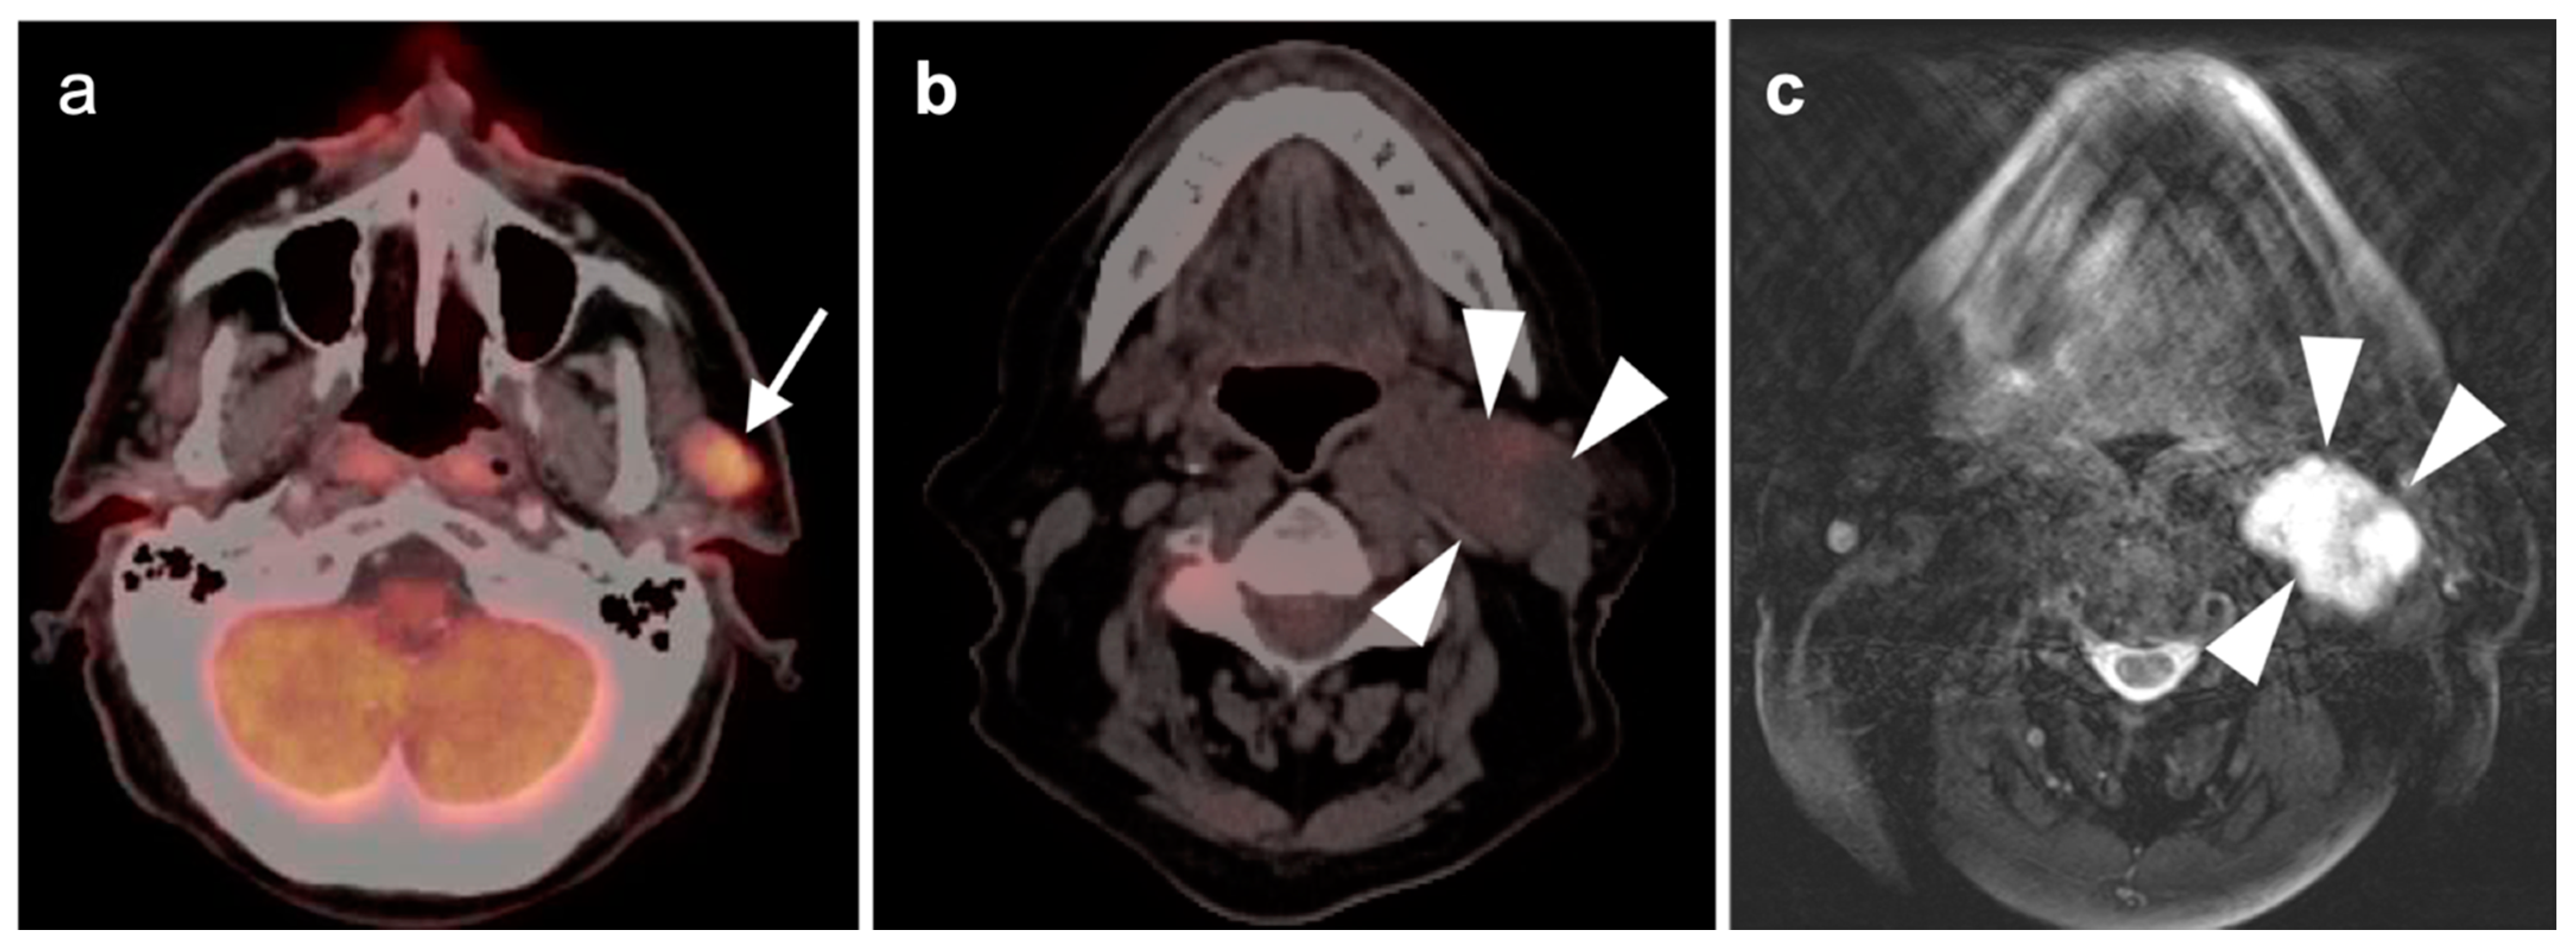

2.5. Major and Minor Salivary Gland, Lacrimal Gland Tumors

- Adenoid cystic carcinoma